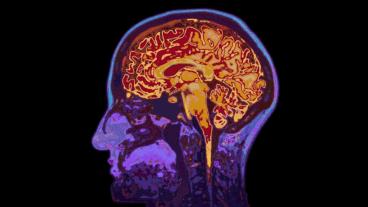

La enfermerdad puede manifestarse por varios motivos: un ACV; un traumatismo craneoencefálico (es decir, un accidente); infecciones o tumores en el cerebro; o enfermedades degenerativas, como el Parkinson o el Alzheimer.

La ciencia ha identificado dos tipos de afasia: motora (o de Broca) y sensorial (o de Wernicke).

La primera se produce por una lesión de la circunvolución frontal inferior izquierda (o de Broca) y áreas adyacentes, provocando que la persona casi no pueda hablar con fluidez y expresar frases cortas. En este caso no se ve afectada la comprensión, y sus síntomas son la deformación de palabras al hablar, la presencia de defectos verbales y de articulación y un estilo telegráfico al expresarse.

La afasia sensorial, por su parte, se da por lesiones de áreas temporo-parietales (área de Wernicke) y sí afecta la capacidad de comprensión. Quienes la padecen son capaces de hablar con oraciones largas carentes de significado, agregan palabras y neologismos, y cambian los vocablos por otros.

Las personas con afasia sensorial quedan incapacitadas casi por completo para comprender su habla y lo que dicen los demás.